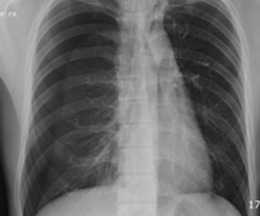

폐기포는 폐 조직 일부가 손상되면서 공기가 빠져나가지 못하고 한쪽에 모여 풍선처럼 부풀어 오르는 현상을 말해요. 병원에서는 이걸 "Bulla" 또는 "Blebs"라고 부르기도 해요. 일반적으로 건강검진이나 흉부 X-ray, CT 촬영 중에 우연히 발견되는 경우가 많아요. 문제는 대부분 별다른 증상이 없어서 본인도 모르게 오래 지내는 경우가 많다는 거죠.

- 흉부 X-ray: 간단하고 저렴하지만, 작은 폐기포는 놓칠 수 있어요.